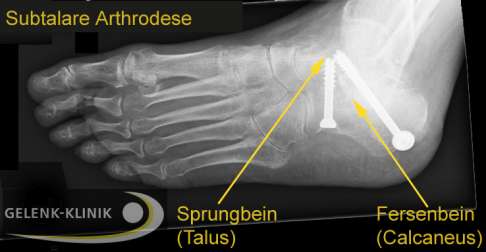

Röntgenbild einer Arthrodese des Subtalargelenks. Das Gelenk zwischen Fersenbein und Sprungbein wird durch Schrauben endgültig versteift. Durch die stabile Unterstützung des in der richtigen Position fixierten Fersenbeines kann die normale Lage des Sprungbeines wiederhergestellt werden. © Gelenk-Klinik

Bei einer subtalaren Arthrodese versteift der Fußchirurg dieses Gelenk therapeutisch. Dazu werden beide Knochen mit Schrauben oder Platten dauerhaft fixiert und miteinander fusioniert.